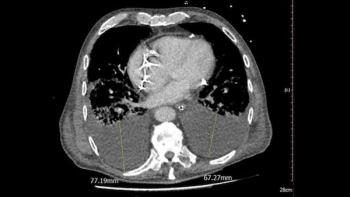

In a multicenter study of over 1,100 patients with COVID-19, pleural effusion was detected on CT scans in nearly a third of patients, who also had significantly higher ICU admission and 30-day mortality rates.